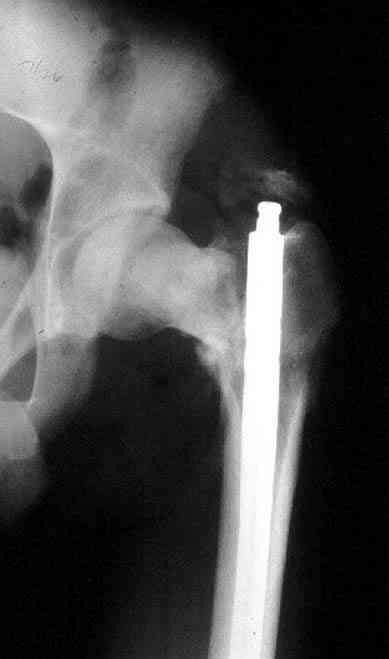

После удаления штифта нет необходимости проведения "стресса" на сращение, лучше провести фиксацию пластиной по два шурупа с каждой стороны.

Минимальный перкутанный доступ без ущерба сохранит сомнительное мозолеобразование и создаст условия для профилактики ложного сустава бедра.

Или при наличии ретроградной техники, короткий штифт с одним блокирующим шурупом дистально, создаст адекватную фиксацию и условия для быстрейшего восстановления.